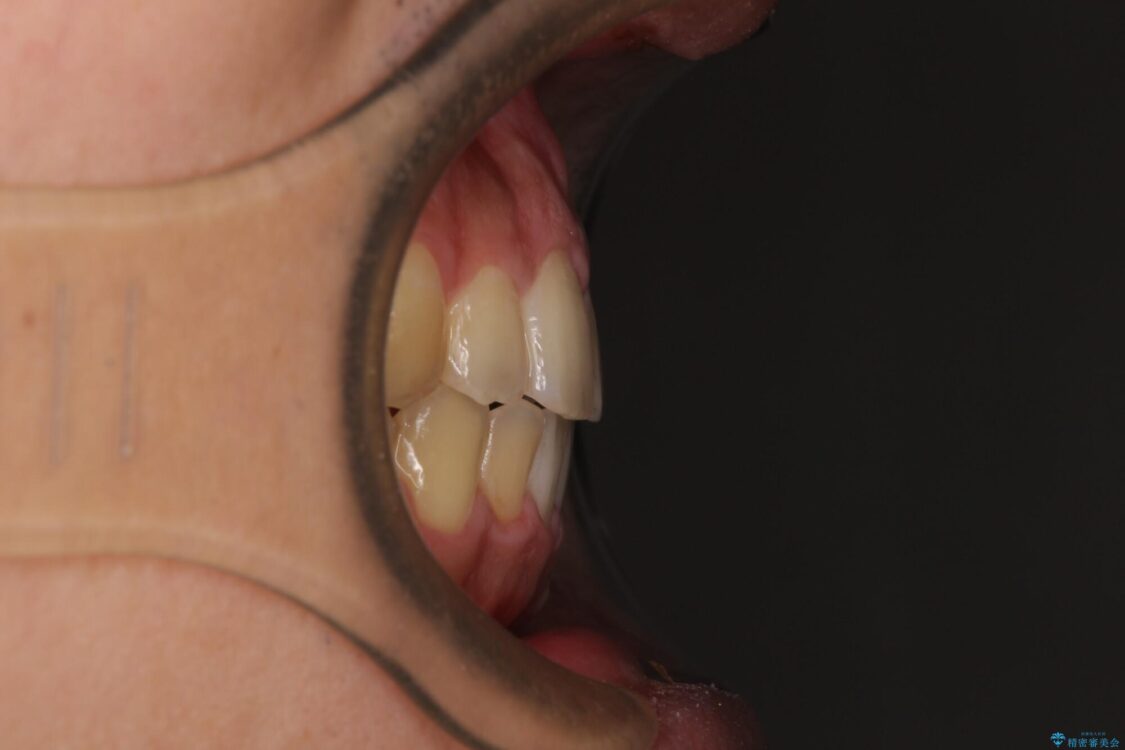

治療途中

• 後戻りでデコボコの前歯 インビザライン矯正治療 治療途中画像